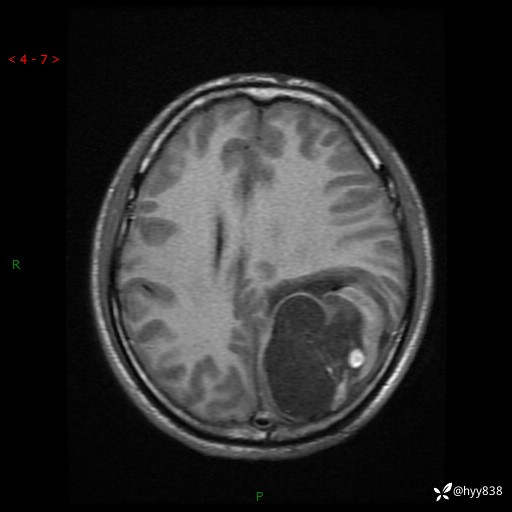

病例年轻小伙,头痛伴呕吐半年,渐进性加重1月。疑难病例,第一次见--结果公布~

性别:男

年龄:21岁

简要病史:头痛伴呕吐半年,渐进性加重1月

颅脑MRI平扫+增强